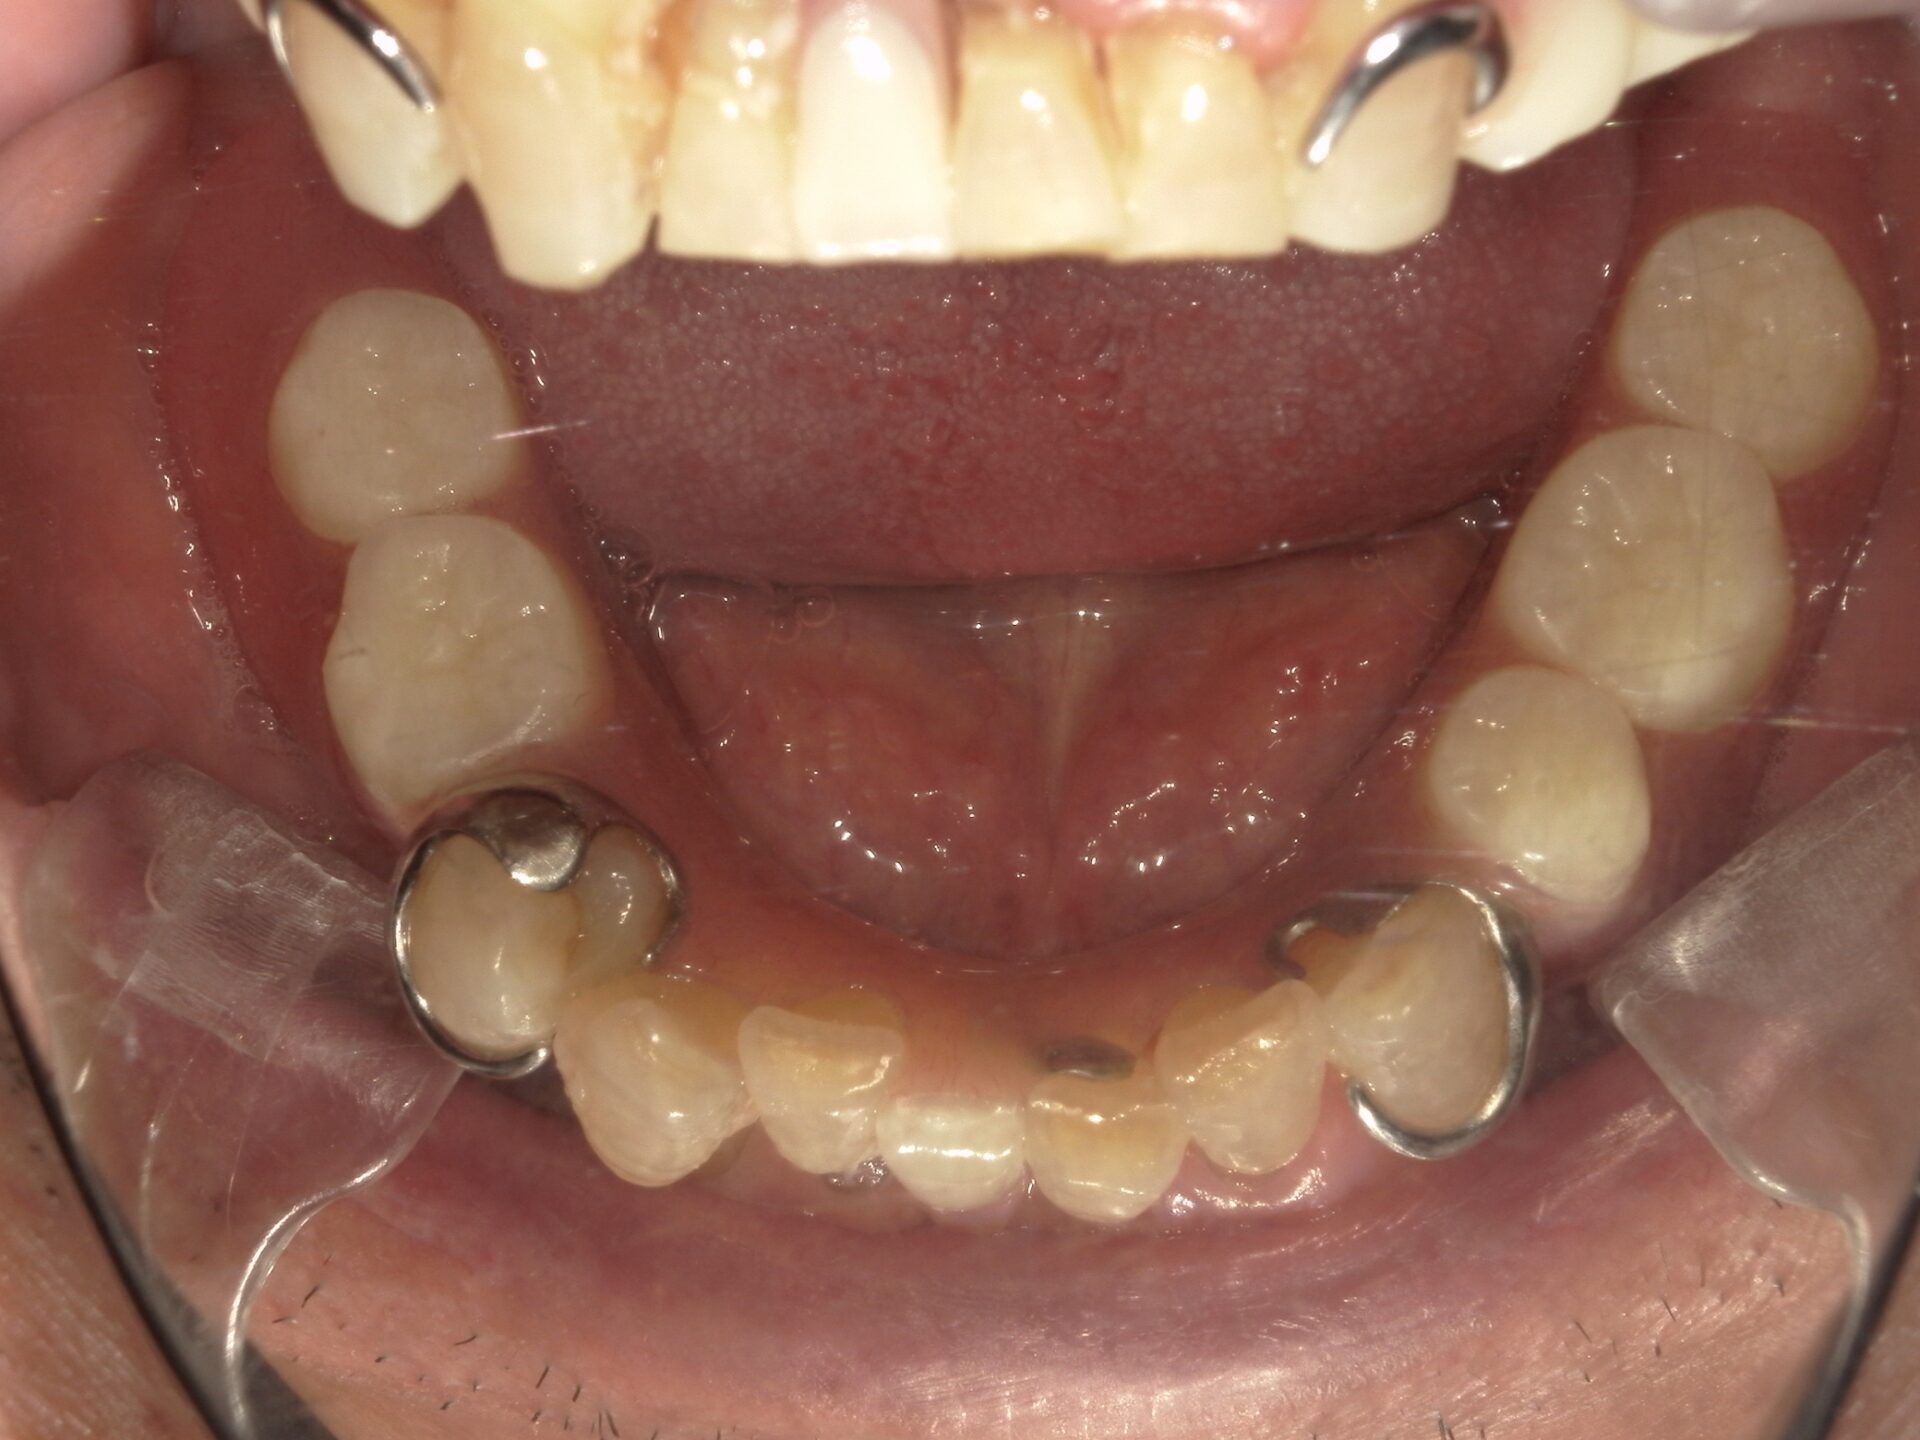

before

患者さんの年齢 50代 男性 症状 何も噛めない 治療内容 インプラント治療(オールオン4) 費用 費用900万(税抜) 治療期間・回数 治療期間2年・通院回数12回 メリット なんでも噛めるようになる 見た目が綺麗 デメリット・リスク 骨造成などで費用が増える場合がある - インプラント治療